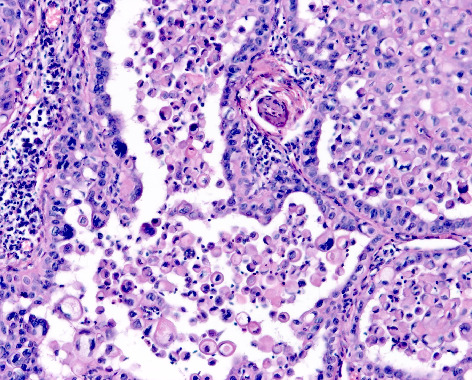

背景:皮肤鳞状细胞癌(CSCC)是全球第二常见的皮肤癌。然而,在澳大利亚和美国等国家,其发病率相对于基底细胞癌(BCC)正在上升。在南非,人口暴露于许多CSCC风险因素,包括高紫外线辐射水平和免疫抑制的高负担,在这方面描述该疾病特征的科学文献仍然明显缺乏。目的:描述南非队列中CSCC的临床、组织病理学和风险特征,以确定可以为当地临床实践提供信息的模式,并指导未来的研究重点。方法:对2019年9月1日至2020年8月31日在Tygerberg学术医院就诊的患者进行回顾性数据分析。从医疗记录中提取人口统计学和临床数据。两名研究评估人员使用预先确定的标准来审查皮肤活检的组织病理学特征。病变的风险分层遵循国家综合癌症网络的指导方针。结果:在一年多的时间里,83例患者诊断出113例CSCCs。参与者主要为Fitzpatrick皮肤光型I(65.1%)和男性(60.2%),中位年龄为73岁,男女比例为1.51:1。bcc与cscc的发病率比为1.71:1。大多数病变存在超过6个月(87.6%),位于头颈部(59.3%)。穿刺活检诊断出62.8%的病变。组织学上63.7%为高分化,40.7%为浸润性。常规CSCCs占病变的75.2%;5.3%为棘溶性高危亚型。77.0%的病变有高复发风险。结论:本研究突出了南非CSCC的异质性,强调了前瞻性、具体情况研究的必要性,以加强全国范围内的预防、早期发现和管理工作。

Background: Cutaneous squamous cell carcinoma (CSCC) is the second most prevalent form of skin cancer globally. However, its incidence is rising relative to basal cell carcinoma (BCC) in countries such as Australia and the United States. In South Africa, where the population is exposed to numerous CSCC risk factors, including high ultraviolet radiation levels and a high burden of immunosuppression, there remains a notable paucity of scientific literature characterising the disease within this context. Aims: To describe the clinical, histopathological and risk profile characteristics of CSCC in a South African cohort to identify patterns that can inform local clinical practice and guide future research priorities. Methods: A retrospective data analysis of patients seen at Tygerberg Academic Hospital between 1 September 2019 and 31 August 2020 was conducted. Demographic and clinical data were extracted from medical records. Two study evaluators used predetermined criteria to review the histopathological features in skin biopsies. Risk stratification of lesions followed the guidelines of the National Comprehensive Cancer Network. Results: Over one year, 113 CSCCs were diagnosed in 83 patients. Participants were primarily Fitzpatrick skin phototype I (65.1%) and male (60.2%), with a median age of 73 years and a male-to-female ratio of 1.51:1. The BCC-to-CSCC incidence ratio was 1.71:1. Most lesions had been present for over 6 months (87.6%) and were located on the head and neck (59.3%). Punch biopsies diagnosed 62.8% of lesions. Histologically, 63.7% were well differentiated, and 40.7% were invasive. Conventional CSCCs comprised 75.2% of lesions; 5.3% were the high-risk acantholytic subtype. A high recurrence risk was found in 77.0% of lesions. Conclusion: This study highlights the heterogeneous nature of CSCC in South Africa and underscores the need for prospective, context-specific research to enhance prevention, early detection and management efforts nationwide.